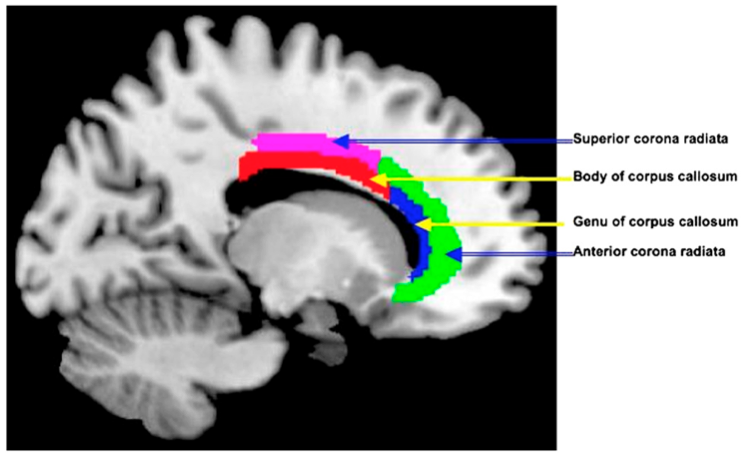

La figure ci-contre montre diverses aires cérébrales pour lesquelles les auteurs ont mesuré une amélioration de la structure de la substance blanche chez les sujets ayant suivis l’IBMT, mais pas chez ceux n’ayant fait que de la relaxation.

L’image ci-contre montre une visualisation des fibres de substance blanche obtenue en IRM par la technique dite du tenseur de diffusion. Dans cette méthode, on observe la diffusion des molécules d’eau dans les fibres et on considère que plus celle-ci est anisotrope, meilleure est l’intégrité et la qualité de la fibre.